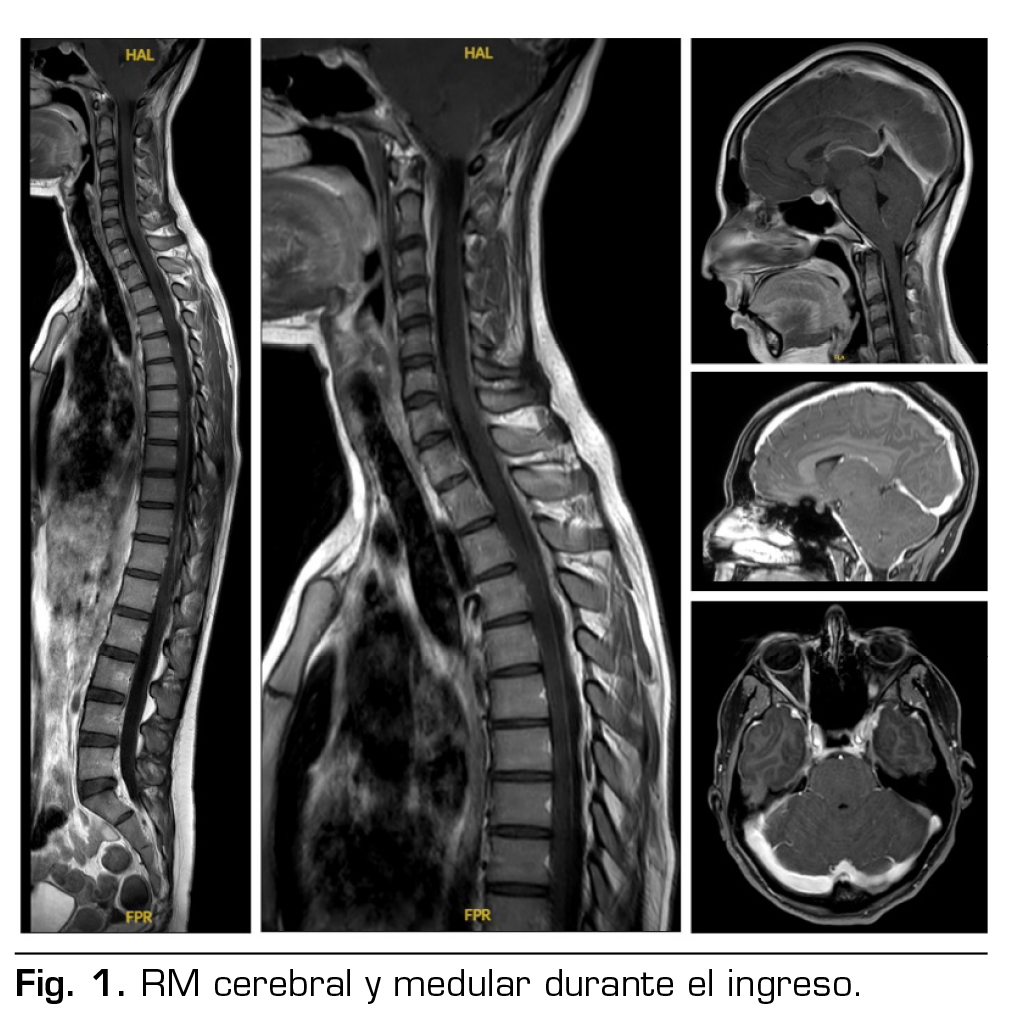

Pruebas complementarias: tomografía computarizada cerebral y analítica normales. RM cerebral y medular: signos de hipotensión intracraneal con engrosamiento dural y pequeñas colecciones laminares en convexidad frontoparietal, colecciones probablemente epidurales en la porción anterior cervical baja y en la región posterior a nivel dorsolumbar (Figura 1).

No se había podido demostrar la existencia de fuga de LCR, pero la presencia de una colección líquida de 57 mm de longitud por delante de la columna anterior del LCR en los segmentos C6-T2, una colección epidural posterior desde T1 hasta T7, y las colecciones en la convexidad frontoparietal, sugerían la localización de las probables fugas, y decidimos realizar un parche hemático no dirigido.

Las tres principales causas y tipos de fuga de LCR en el síndrome de SIH son: desgarro ventral de la duramadre de forma espontánea, a menudo en el contexto de una enfermedad degenerativa de la columna vertebral (tipo I); divertículos meníngeos, que han sido asociados a anomalías del tejido conectivo (tipo II); y fístulas venosas de LCR (tipo III), (2,4,5,6). En cuanto a las pruebas de imagen, podemos caracterizarlas según la localización anatómica: cerebral o medular. Las imágenes cerebrales proporcionan una visión de las secuelas de la pérdida de LCR y son muy útiles para el diagnóstico inicial; el signo más típico es el descenso de las estructuras intracraneanas y un realce paquimeníngeo en la RM. Las imágenes medulares son útiles para buscar el origen de la fuga (5,9,10,11,14). Se han encontrado colecciones extradurales de LCR en aproximadamente la mitad de los pacientes con SIH (2). Las fugas se han localizado más frecuentemente a nivel torácico y cervical (8).